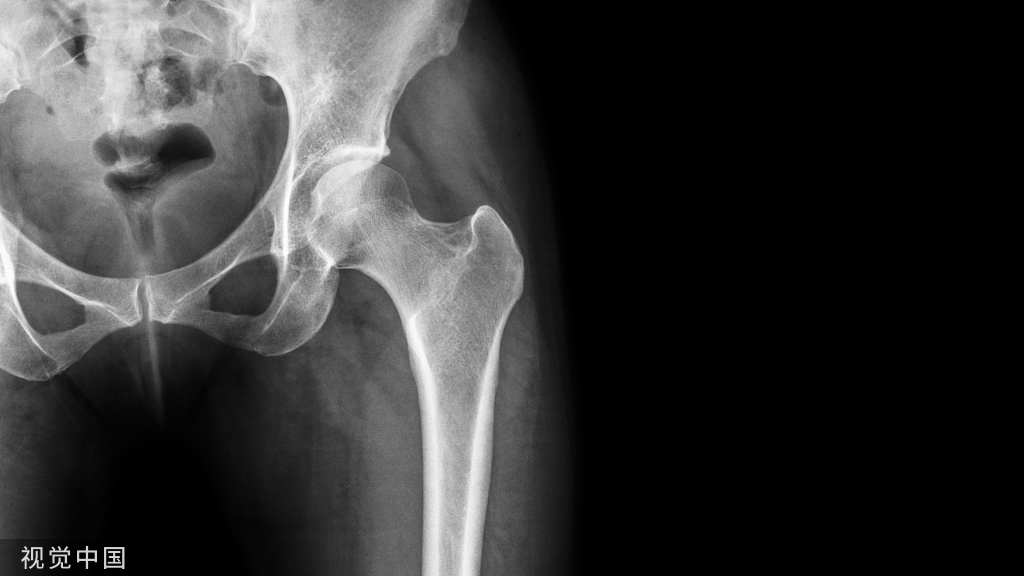

年龄:2岁性别:男病史:O型腿,走路困难

X线

X线见双胫骨内翻,双胫骨近侧干骺端增宽,内侧皮质增厚呈鸟嘴样

结论:Blount病